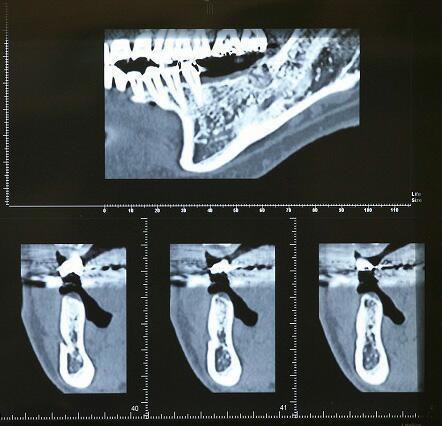

抜歯4ヶ月後のCTエックス線

輪切りにされた下顎骨

・真上の写真の楔状の切れ目はオトガイ神経の出口でインプラント埋入手術時は避けなければならない場所です

・このCTレントゲンによってインプラント埋入手術の安全性が大変高まっています

・このCTレントゲンを検討し、インプラント体(フィクスチャー)埋入場所、太さ等を決めていきます